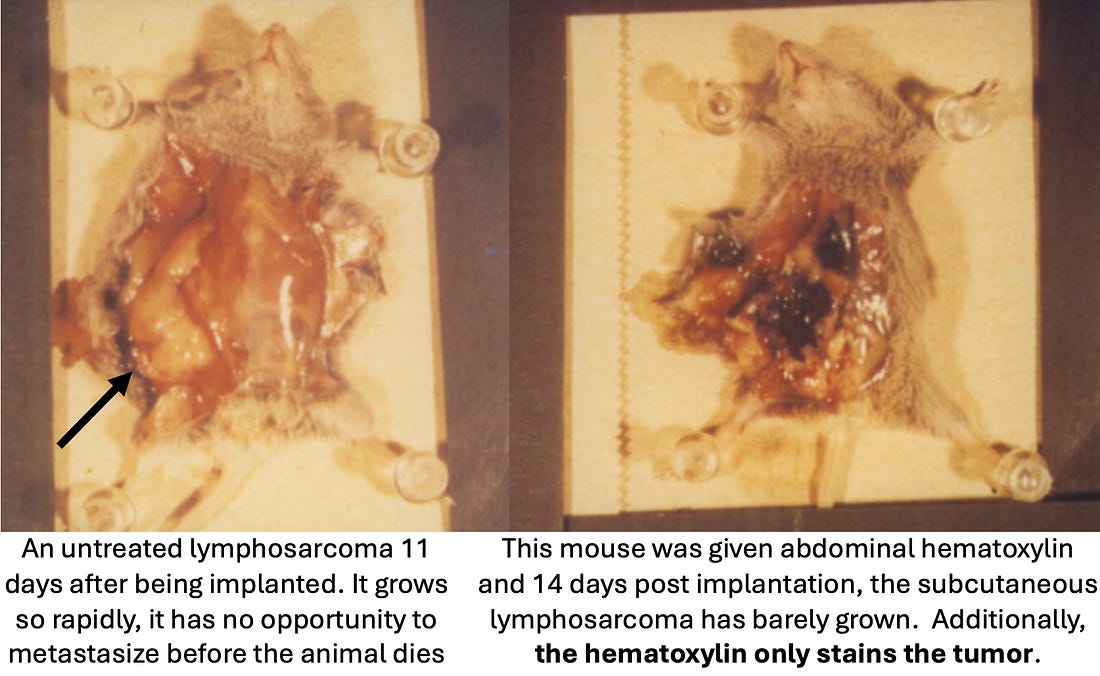

To do so, Rogers implanted mice with rapidly growing lymphosarcoma cells (which typically resulted in death 11 days), then sacrificed and dissected them shortly before their expected time of death and visually examined everything (including under both a light and electron microscope). The mice in turn received either nothing, DMSO alone, hematoxylin alone (which was dissolved in saline through heating and agitation), or varying doses of D-hematoxylin (0.2mL of 90% DMSO mixed with either 2, 5, 8 or 12mg of hematoxylin in DMSO). DMSO and hematoxylin alone were observed to have no side effects, but also do not affect the growing cancers, while D-hematoxylin inhibited the cancers in a dose dependent fashion (and did so without side effects or affecting non-cancerous tissue). Note: since IVs (which are typically the most potent way to administer DMSO or D-hematoxylin) are challenging to give to mice, Rogers instead administered the treatments through intraperitoneal or subcutaneous injections and oral feeding (and likewise Tapia in his LD50 study only did intraperitoneal injections). There, Rogers discovered that subcutaneous and intraperitoneal D-hematoxylin gave similar notable results, while oral D-hematoxylin produced similar but less extensive results (which dovetails with Tucker’s observation he could also obtain clinical results with oral D-hematoxylin). With intraperitoneal D-hematoxylin, the lowest 2mg dose caused slight alterations of the tumor cell morphology, 5mg caused the same changed but in a larger area, 8mg sometimes shrank the tumor, while 12mg caused a complete destruction of the tumor and shrank the tumor by approximately 33% (which extended the mice’s lifespan by approximately 27%). Additionally, while the mice were typically sacrificed four days after completing five D-Hematoxylin treatment, in one case they were instead sacrificed a day after, and there, early stages of degeneration were observed, demonstrating D-hematoxylin initiates a therapeutic process that continues long after the treatment has been discontinued. Additionally, at all doses, D-hematoxylin was found to affect the tumor’s center first, then spread outward, sparing the periphery from the effects observed throughout the rest of the tumor. However, at higher doses (8 or 12 mg), minor changes were also detected in the peripheral regions. This pattern is highly unusual, as chemotherapy agents typically target the cancer from the periphery inward (along with a smaller number that destroy the cancer in a more scattered and heterogeneous manner). This in turn suggests D-hematoxylin is able to penetrate the barriers which normally allow cancer cells to resist chemotherapies (which as I showed previously DMSO has been demonstrated to do for other chemotherapies). Similarly, when individual cells were observed, the damage initially began in the nucleus (with the appearance of nucleolar lesions and loss of peripheral chromatin nuclei), suggesting D-hematoxylin had an affinity for DNA (which hematein does). Following this, the cancer cells, in successive stages, began to break down and digest themselves (autolysis), a death process different from the apoptosis typically observed when DMSO alone eliminates cancers (that was potentially due to DMSO releasing digestive enzymes from lysosomes). Finally, as this progressed, debris from other tumors increased and white blood cells began to invade the tumors to eliminate them. Note: in the mice, if cancer debris increased too quickly, it could cause kidney failure (as there was too much for the kidneys to process. Subsequently, Morton Walker analyzed that dissertation and concluded that D-hematoxylin was dissolving the extracellular matrix (which can also been seen in many other pictures within the study) and that this matrix dissolving deprived the cancer cells of necessary nutrients, causing them to starve (which likewise could explain the gradual degenerative process D-hematoxylin initiates in cancer cells starting from the center rather than the periphery). Note: other processes could also explain these changes (e.g., anoikis, a form of cell death triggered by detaching from the extracellular matrix rather than starvation, could trigger cell death beginning in the center of the tumor, or alternatively, the loss of the ECM could be an effect of cell death rather than a cause and not play a contributing role to the changes observed). Sadly, other than Rogers’ dissertation (which just scratches the surface of what was happening), no one has conducted the cellular experiments to determine why D-hematoxylin works. Fortunately, a team in Ecuador (where research is fairly affordable) is presently trying to get the funding to do that research, so if anyone could help support funding that research, please let us know (e.g., in the comments below). Note: the only other study I have been able to locate that assessed the effects of DMSO combined with hematoxylin was a study that found DMSO effectively washed hematoxylin away from starch granules in pollen cells but not from the nucleus, again implying D-hematoxylin has a special affinity for the nucleus of cells. This study, in turn, was conducted because hematoxylin would consistently darkly stain starch granules, making it impossible to see out the pollen cell’s nucleus. Protein Kinase CK2Protein Kinase CK2 , when dysregulated, has been implicated in hundreds of diseases (e.g., viral infections including COVID-19, autoimmune diseases, and neurological conditions). Of those, its best known for playing a key role in cancer (e.g. its activity is often elevated in various cancers, which contributes to tumor progression and poor prognosis). Some of its carcinogenic effects include: •CK2 phosphorylates hundreds of proteins which allows it to both activate key cancer signaling pathways such as PI3K/Akt, mTORC1, and β-catenin1,2 (which promotes cancer cell proliferation, survival, angiogenesis, invasion, and metastasis).and to inhibit key tumor suppressors like PTEN and p53. •CK2 modulates the Warburg effect, hence triggering a metabolic switch where cancer cells stop relying on oxygen for energy production (something many over the years believed is a root cause of cancer). Additionally, CK2 also preserves mitochondrial function to support the high energy demands of growing tumor. •Cancer CK2 activity suppresses the immune system’s ability to eliminate cancer cells, while numerous studies show that inhibiting CK2 activity enhances the immune system’s ability to eliminate cancers. •CK2 makes cancer cells resistant to programmed cell death and hence makes them continue to proliferate. Additionally, CK2 makes cancer cells resistant to anoikis